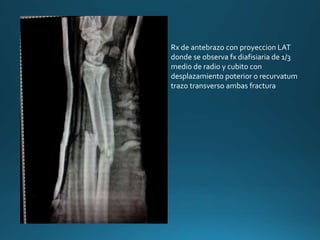

Rx de antebrazo con proyeccion LAT

donde se observa fx diafisiaria de 1/3

medio de radio y cubito con

desplazamiento poterior o recurvatum

trazo transverso ambas fractura